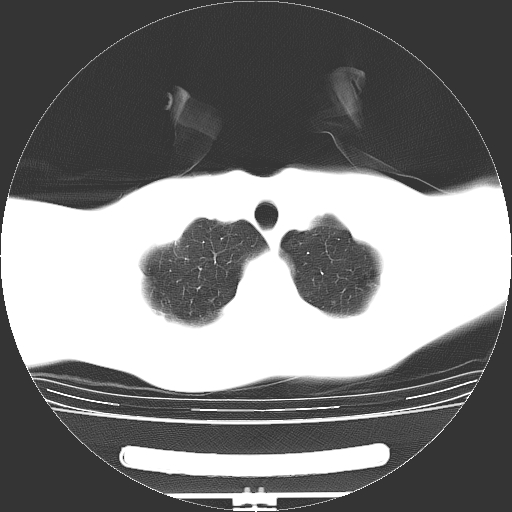

标题: CT19767:男,20岁,右侧气胸行闭式引流术后五天CT检查。 [打印本页]

男,20岁,右侧气胸行闭式引流术后五天ct检查看肺内是否有肺大泡,纵隔窗未见异常,未上传。

1)右侧胸腔闭式引流术后导管留置。2)右肺未见肺大泡。

未见肺大泡,还有微量气体。